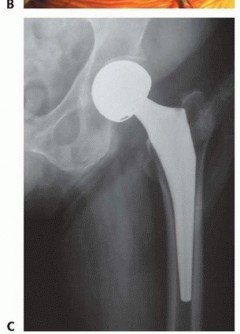

نصف مفصل الورك هو إجراء جراحي يتم فيه استبدال الجزء الكروي العلوي من عظم الفخذ (رأس الفخذ) فقط، بينما يظل التجويف الحقي (Acetabulum) الطبيعي في عظم الحوض سليمًا. يتم استبدال رأس الفخذ المكسور أو التالف بمكون اصطناعي (غرسة) يتكون عادةً من ساق معدنية تُدخل في عظم الفخذ ورأس كروي يحل محل رأس الفخذ الأصلي.

يختلف هذا عن الاستبدال الكلي لمفصل الورك (Total Hip Arthroplasty - THA) الذي يتضمن استبدال كلا الجزأين، رأس الفخذ والتجويف الحقي، بمكونات اصطناعية. يتميز نصف مفصل الورك بكونه إجراءً أقل تعقيدًا وأقل تدخلاً من الجراحة الكلية، مما يجعله خيارًا مفضلاً في حالات معينة.